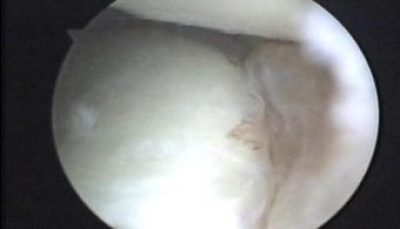

Se observa la desinserción del complejo cápsulo ligamentario anterior, lesión de Bankart